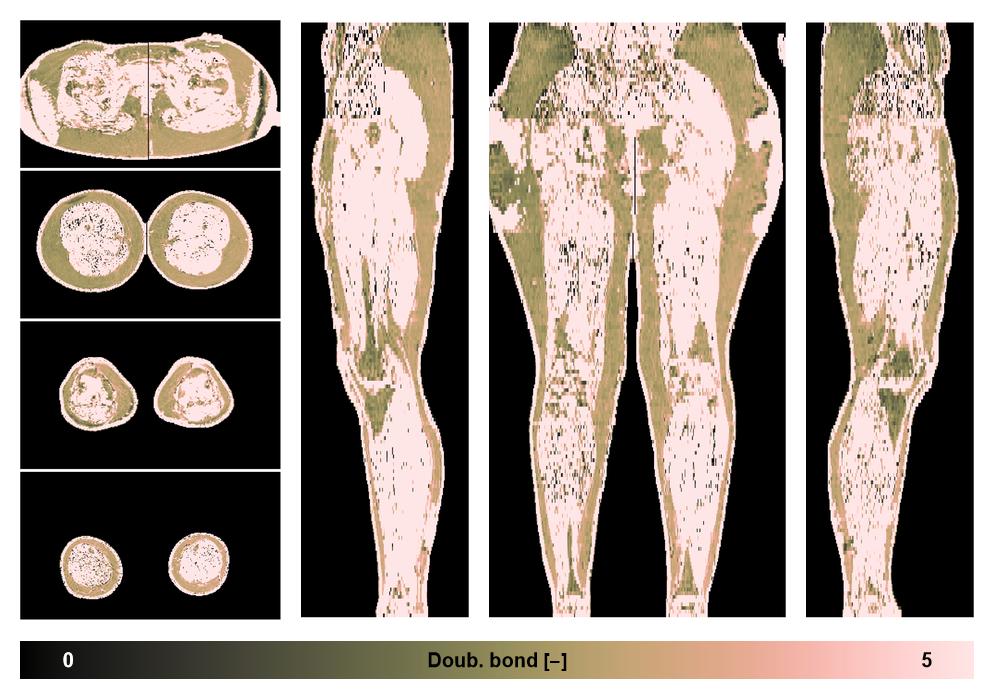

• Number of double bonds in subcutanious fat

Number of double bonds in subcutanious fat.